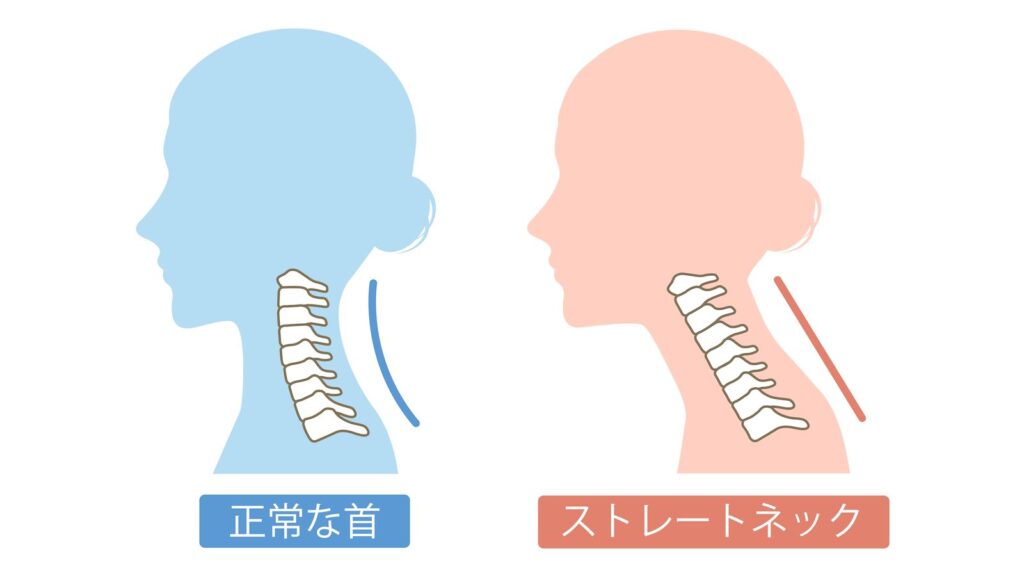

これらの筋肉が縮こまることで、

- 顔が下を向いた姿勢

- 首が前に倒れた状態(ストレートネック傾向)

になりやすくなります。

その姿勢では奥歯が噛み合いやすくなり、 さらに首の前の筋肉・咬筋・側頭筋が緊張 → 食いしばりが助長される という悪循環に陥ります。